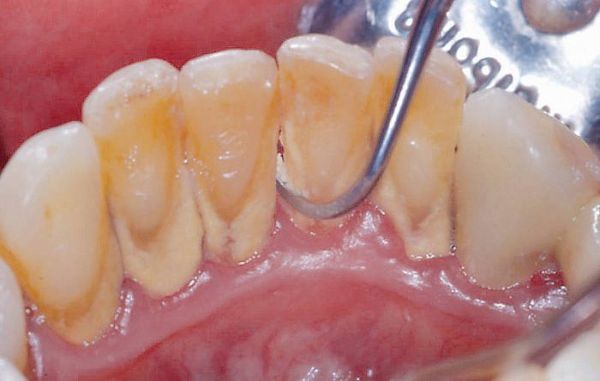

Hình ảnh lấy cao răng

Bước 2: Cạo vôi bằng máy siêu âm hiện đại

Sử dụng đầu sóng siêu âm nhập khẩu châu Âu, giúp loại bỏ mảng bám cứng nhanh chóng mà không gây đau hay chảy máu.